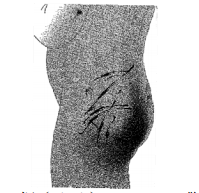

39 小孩臀部的傷(如圖),是何種受傷機轉造成的?

(A)捏(pinch) (B)鞭打(belt) (C)拳打(knuckle) (D)掌摑(slap)